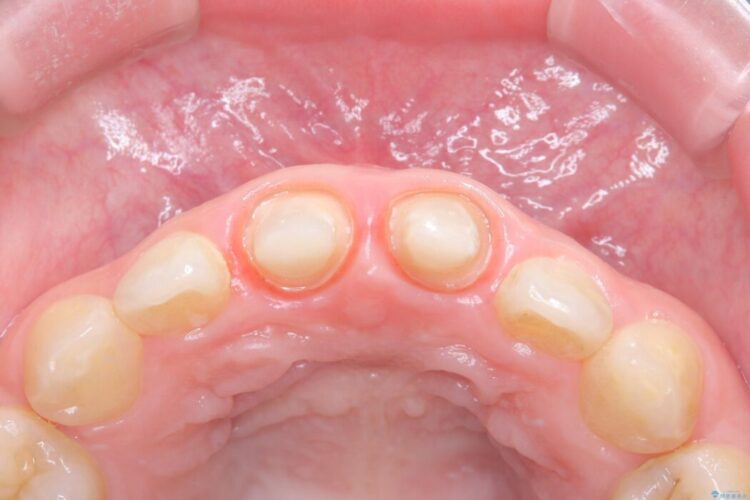

精密検査の結果、単に被せ物が合っていないだけでなく、その下の歯の根の治療(根管充填)が不十分で、再感染のリスクが高いことが分かりました。そのため、被せ物を新しくする前に、まず顕微鏡などを用いた精密根管治療を行いました。その上で、最も見た目が自然なオールセラミッククラウンで修復する計画です。これにより見た目の改善と歯の寿命の長期化を目指しました。

治療は、再感染の原因となっていた粗な根管充填材を丁寧に取り除く精密根管治療から開始しました。治療中はラバーダムと歯科用顕微鏡を使用し、根管内を徹底的に清掃・消毒。根の先まで緊密に薬を詰めることで、再発リスクを最小限に抑えました。根管治療の完了後、歯ぐきの状態を整え、周囲の歯と調和するオールセラミッククラウンを作製。金属を一切使わないため、透明感のある自然な仕上がりとなり、長年の見た目のコンプレックスも解消。歯の内部から表面までを根本的に改善することができました。